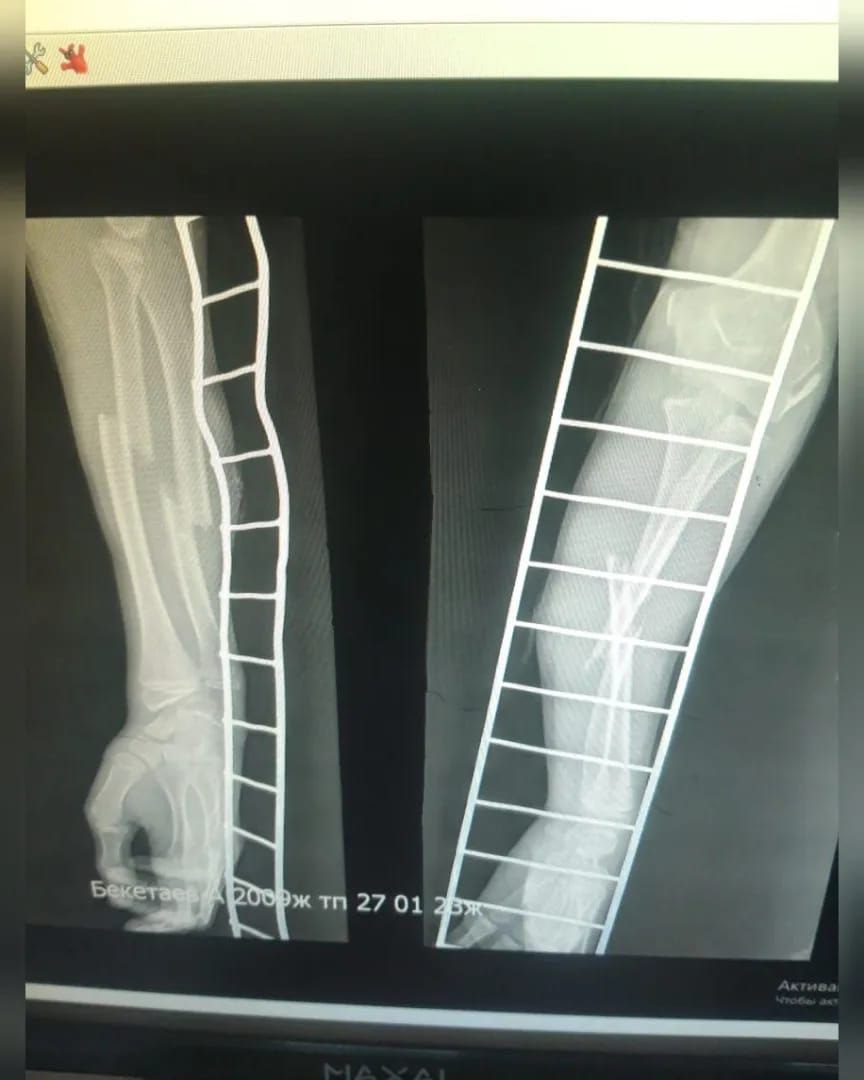

По её словам, у подростка открытый перелом двух костей со смещением. По данному факту завели уголовное дело по статье 107 УК РК, но производство сразу прекратили из-за возраста агрессора. Он не понесёт уголовную ответственность. Дело также не направили в суд по статье 140 УК РК - "Неисполнение обязанностей по воспитанию несовершеннолетнего" в отношении родителей нападавшего.

В управлении полиции Тараза сообщили, что 14 февраля во второй отдел полиции города обратилась 38-летняя местная жительница. Она сообщила, что на её 14-летнего сына напал 13-летний подросток 27 января около 19:00.